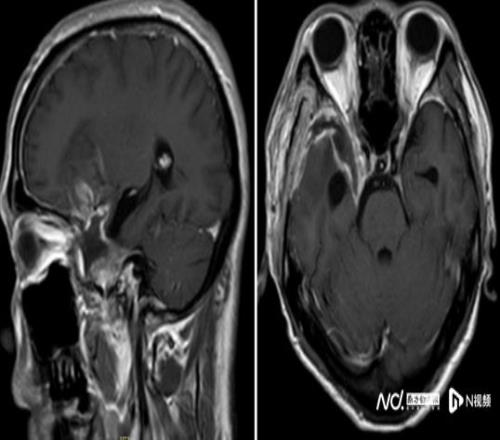

经过近8个小时的精细操作,肿瘤被完整切除,重要神经血管结构完好保留。术后患者恢复良好,顺利出院,经过积极康复后,陈叔有望重回马拉松赛场。